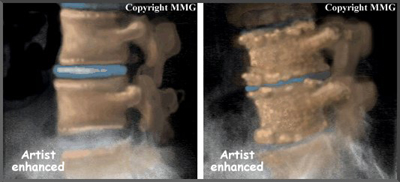

Disc degeneration follows a predictable pattern. First, the nucleus in the center of the disc begins to lose its ability to absorb water. The disc becomes dehydrated. Then the nucleus becomes thick and fibrous, so that it looks much the same as the annulus. As a result, the nucleus isn't able to absorb shock as well. Routine stress and strain begin to take a toll on the structures of the spine. Tears form around the annulus. The disc weakens. It starts to collapse, and the bones of the spine compress.

Related Document: FYZICAL Central Nampa's Guide to Low Back Pain